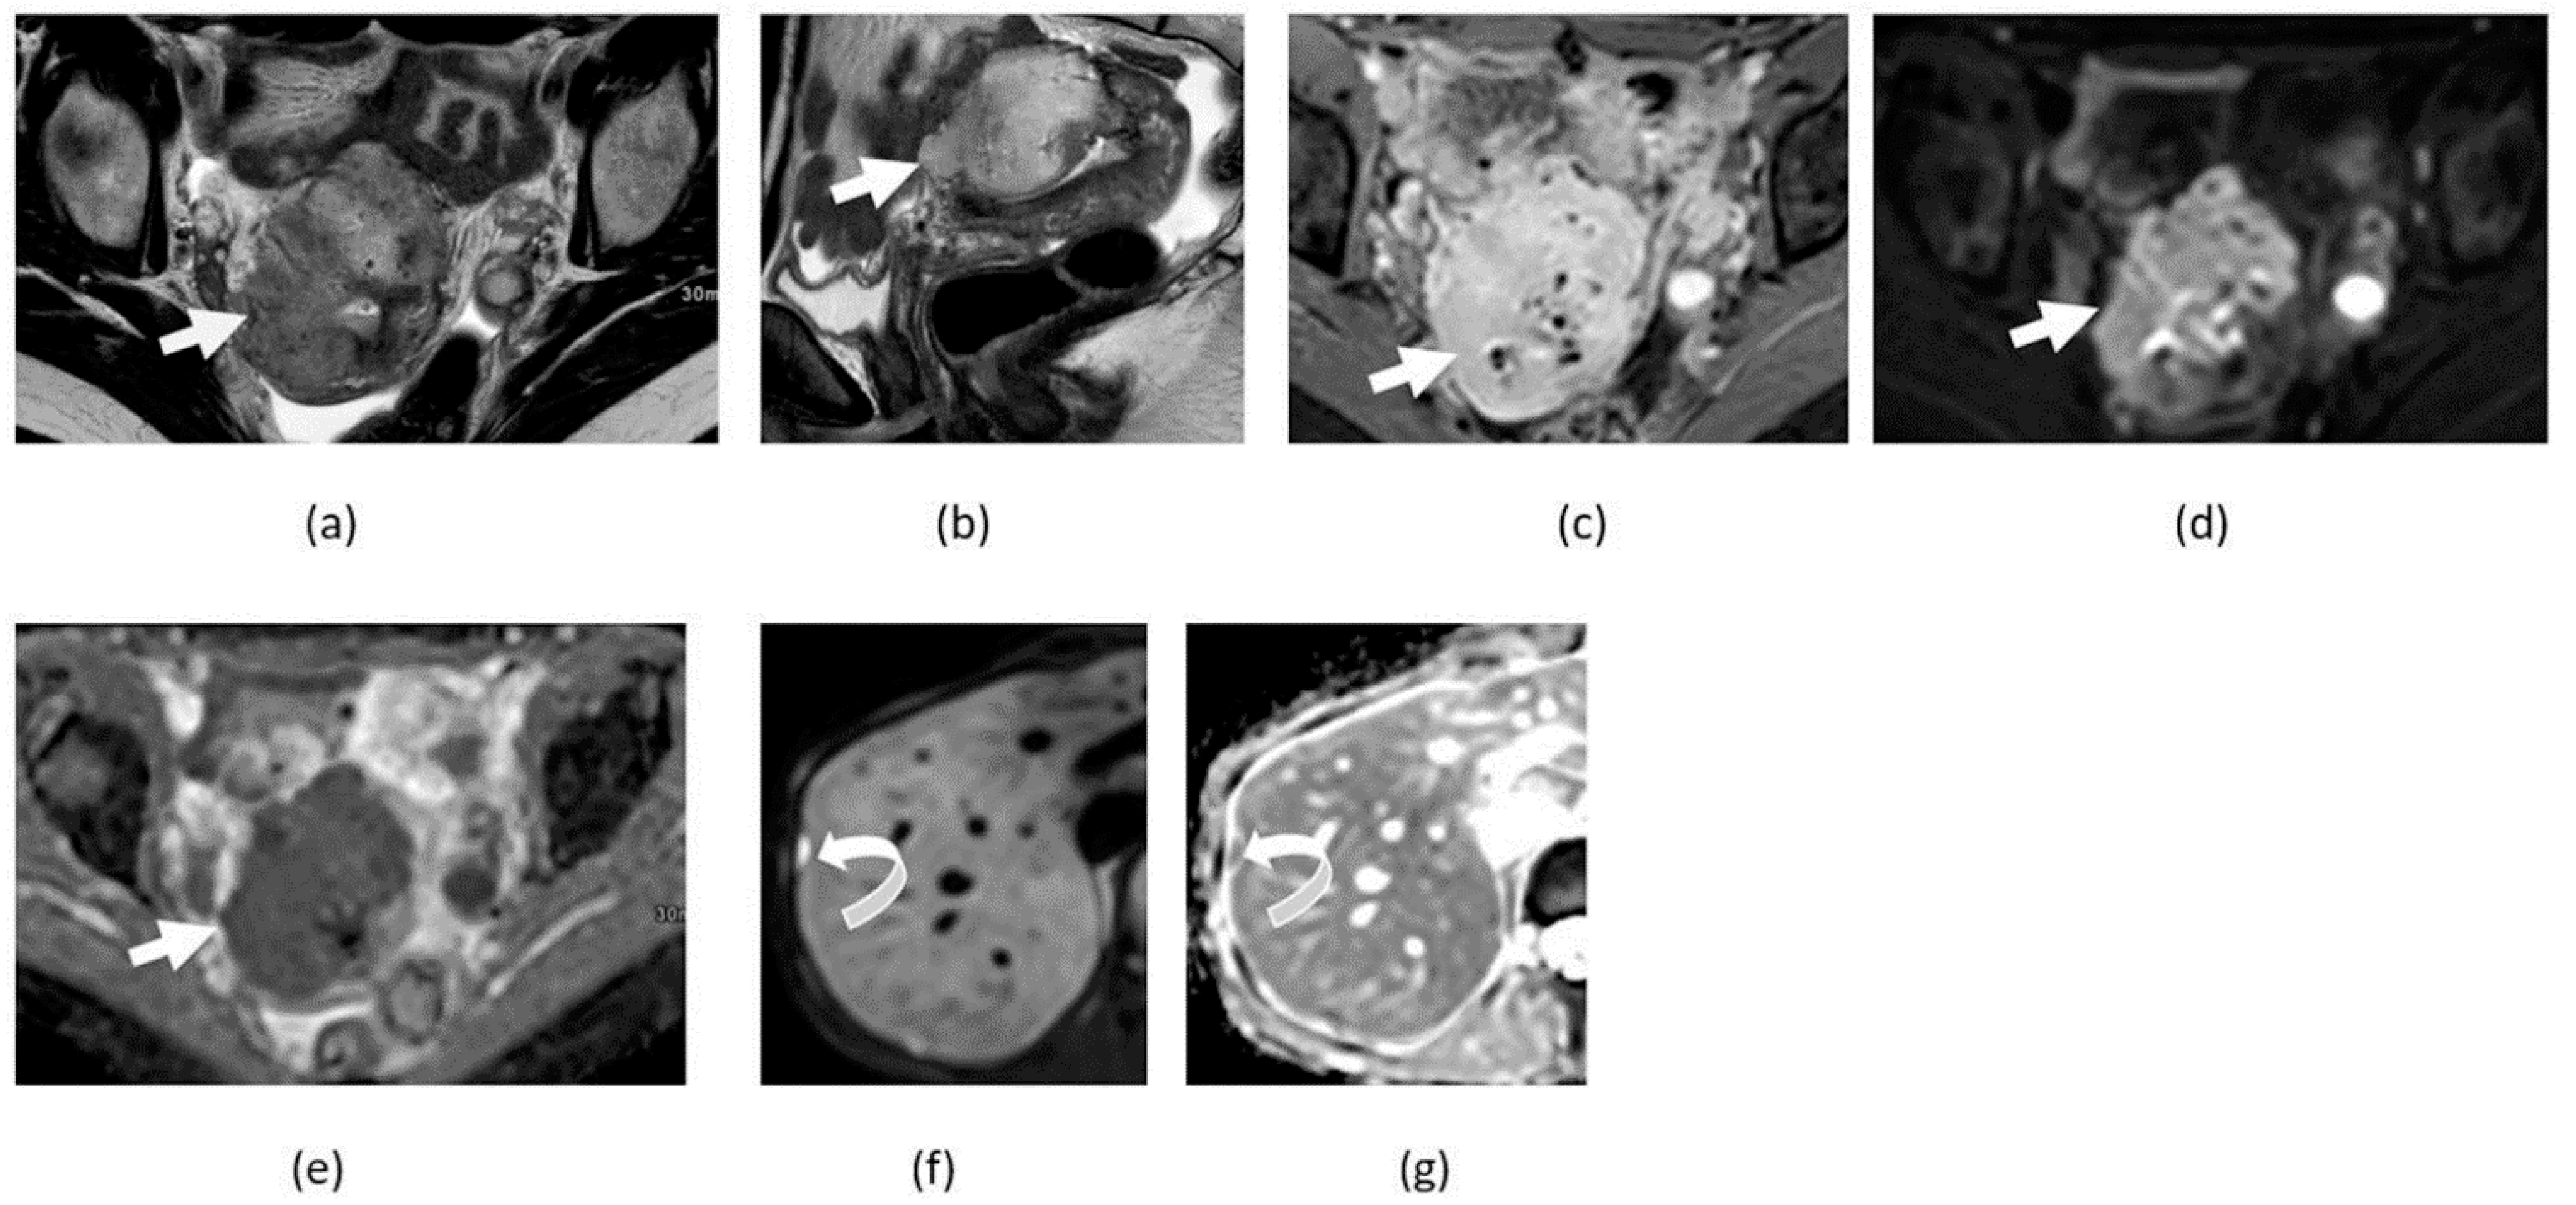

3.5. Mature Cystic Teratoma

3.6. Ovarian Fibroma, Fibrothecoma, and Thecoma